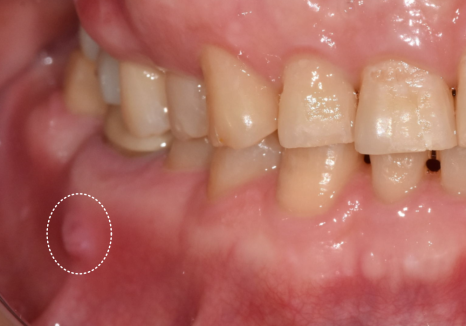

얼마 전 오른쪽 아래 어금니에

여드름 같은 게 생겼다며

저희 치과를 찾으신 환자분의 사례예요.

입안을 살펴보니 잇몸 겉에

뽈록한 고름 주머니가 보였는데,

환자분께서는 아프지도 않고 금방 가라앉길래

치료를 계속 미뤄오셨다고 해요.

하지만 잇몸 겉에 증상이 나타났다는 건,

잇몸 뼈는 훨씬 깊은 곳에서부터

녹고 있다는 뜻입니다.